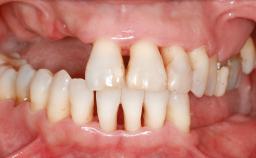

A 45-year-old woman with a completely edentulous maxilla was referred to evaluate the possibility of rehabilitation with an implant-supported prosthesis. This patient was healthy and a non-smoker. She had been wearing a maxillary complete denture opposing a natural mandibular dentition since her twenties. This situation had resulted in progressive resorption of the alveolar ridge, repeatedly creating a need for relining the denture. Twenty years later, despite multiple adaptations and the use of “glues” the denture was unstable and causing the patient psychological and functional discomfort.

Defining Characteristics Fully edentulous upper jaw to be rehabilitated with an implant-borne fixed dental prosthesis

Loading Protocol Conventional or early